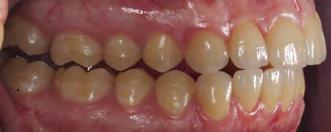

08 — Preparaciones terminadas de los dientes anteriores en el maxilar superior e inferior (preparación parcial). 08b

Si es posible, para la cementación adhesiva se coloca un dique de goma para aislamiento absoluto. Alternativamente, antes de la cementación se coloca un hilo de retracción de grosor 00 en el surco, para tener buen acceso a los márgenes de la preparación (Fig. 12). Los dientes adyacentes se aíslan con cinta de teflón. Normalmente colocamos las coronas en pares. Después de grabar con ácido fosfórico al 37 %, el muñón del diente muestra que casi toda la preparación entera está en la zona del esmalte. La dentina es visible solo en áreas aisladas, expuesta por la actividad parafuncional de la paciente.

Los dientes anterosuperiores y anteroinferiores, así como los dientes posteriores del maxilar inferior, han sido restaurados de forma definitiva. La restauración provisional de los dientes posterosuperiores aún permite pequeñas correcciones en el área de las superficies oclusales.